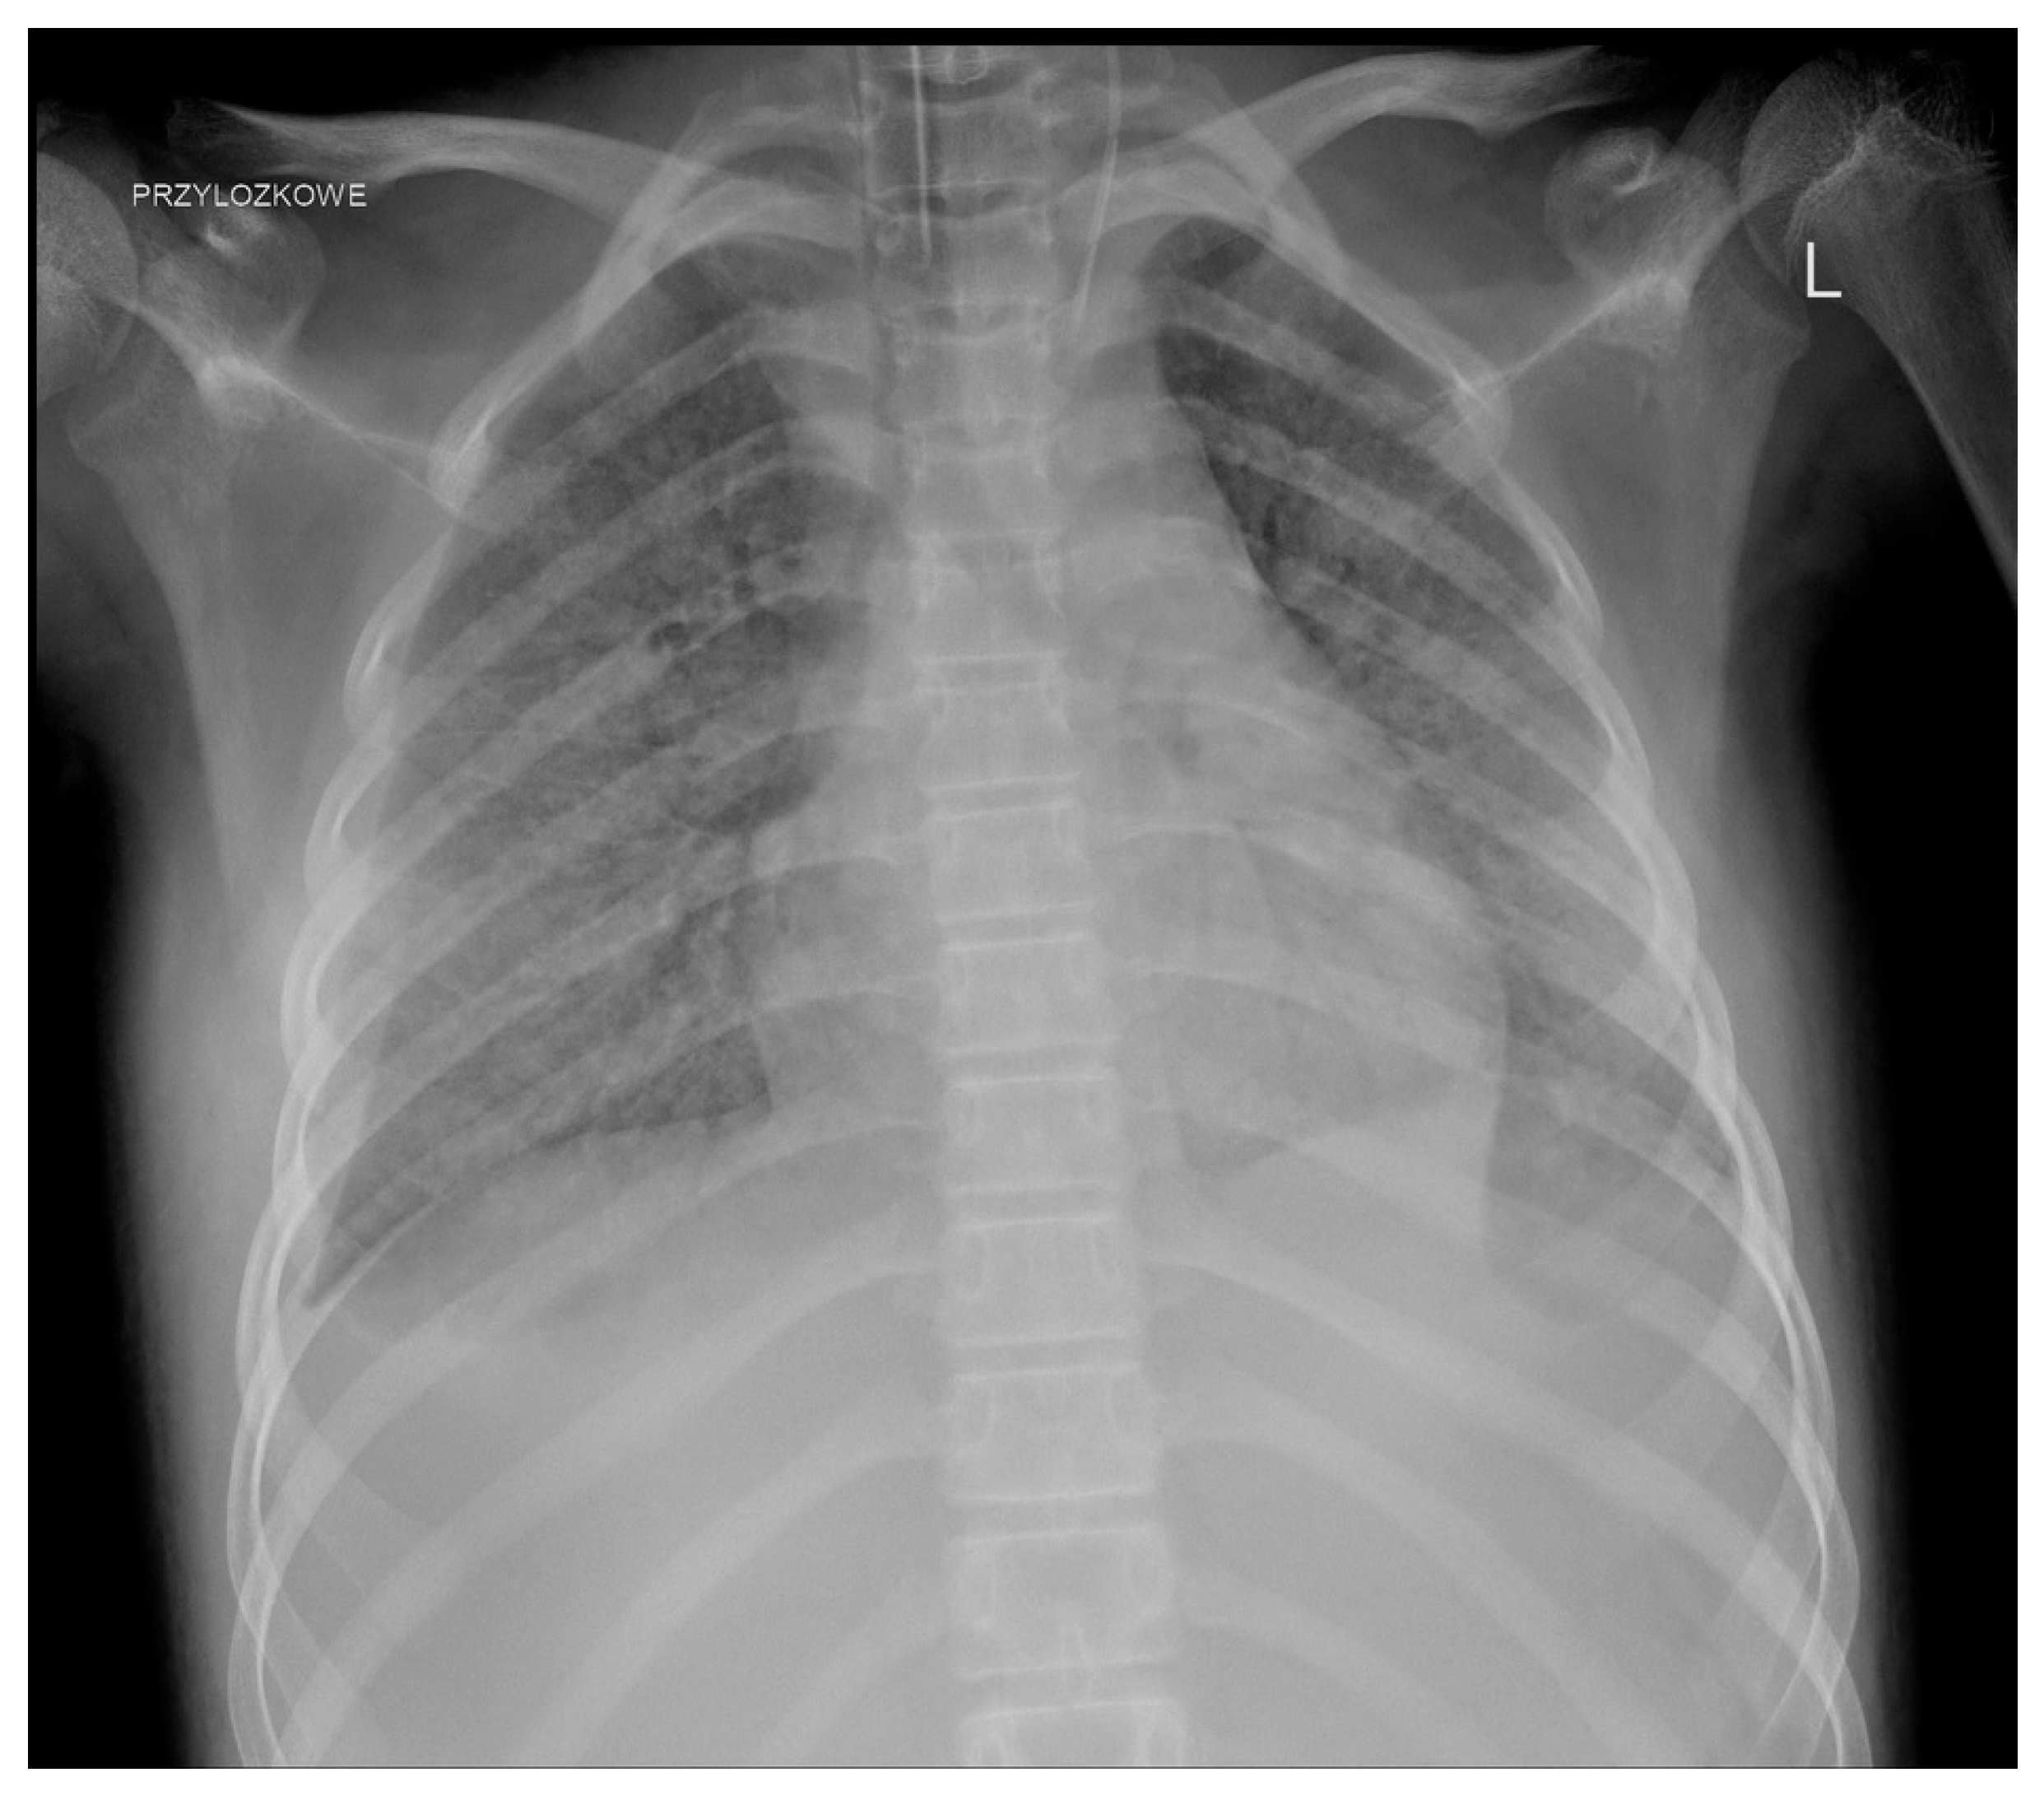

We observed a few complications related to GC administration. One patient developed an anaphylactic reaction during the second transfusion. One girl, who required hospitalisation in the ICU as a result of infection, about 2 h after the administration of the GC, developed shock symptoms with the deterioration of the general condition and circulatory and respiratory instability; transfusion-related acute lung injury (TRALI) was diagnosed after further investigation (Figure 3).

Figure 3.

TRALI after GC transfusion.

A non-negligible issue is the side effects. Initially, side effects, mainly from the respiratory system, led to the suspension of GC use [6]. The significant development of serological methods has significantly improved the safety of GC use. The most common adverse reactions are not markedly different and do not occur more frequently than during the transfusion of other blood products [6]. Some of them can be avoided by proper donor screening, appropriate pretransfusion premedication (such as antihistamines, acetaminophen, and steroids), and maintaining adequate intervals between the administration of other medications (e.g., amphotericin B) [17]. Gea-Banacloche summarised the most common toxicities, including fever, HLA sensitisation, pulmonary reactions, and CMV infection (if CMV-positive donors are used) [10]. Fever appears to be the most common complication. Alloimmunisation seems particularly problematic in the context of further anticancer treatment (in one patient, we struggled for a long time with the consequences of this complication). The risk of transfusion-transmitted infection is low as donors are routinely screened for infectious diseases, but it still exists [9]. Pulmonary complications, which are considered acute transfusion-related adverse events, appear to cause particular (and justified) concerns. Grigull et al. reported the need for the temporary escalation of respiratory support in patients undergoing mechanical ventilation, worsening of pulmonary symptoms in two children with viral pneumonia, and even the development of progressive respiratory failure during GC transfusion [18]. In a systematic review covering studies from 1966 to 2006 on granulocyte transfusions in neutropenic children, the authors observed pulmonary complications in only seven recipients, ranging from mild to more severe respiratory symptoms, but TRALI was not reported. They concluded that novel methods of leukapheresis have significantly reduced the risk of severe pulmonary complications that were observed in the past [19]. However, such reports still appear even in significantly more recent studies. Díaz et al. in a group of 13 patients with underlying acute infection observed respiratory symptoms in 6 patients (46%) including hypoxemia and tachypnea that were likely secondary to GC transfusions [34]. Weingarten et al. described one episode of life-threatening grade 4 dyspnoea (in a cohort of 21 patients) [28]. TRALI, which was diagnosed in one of our patients, remained in close association with GC administration.